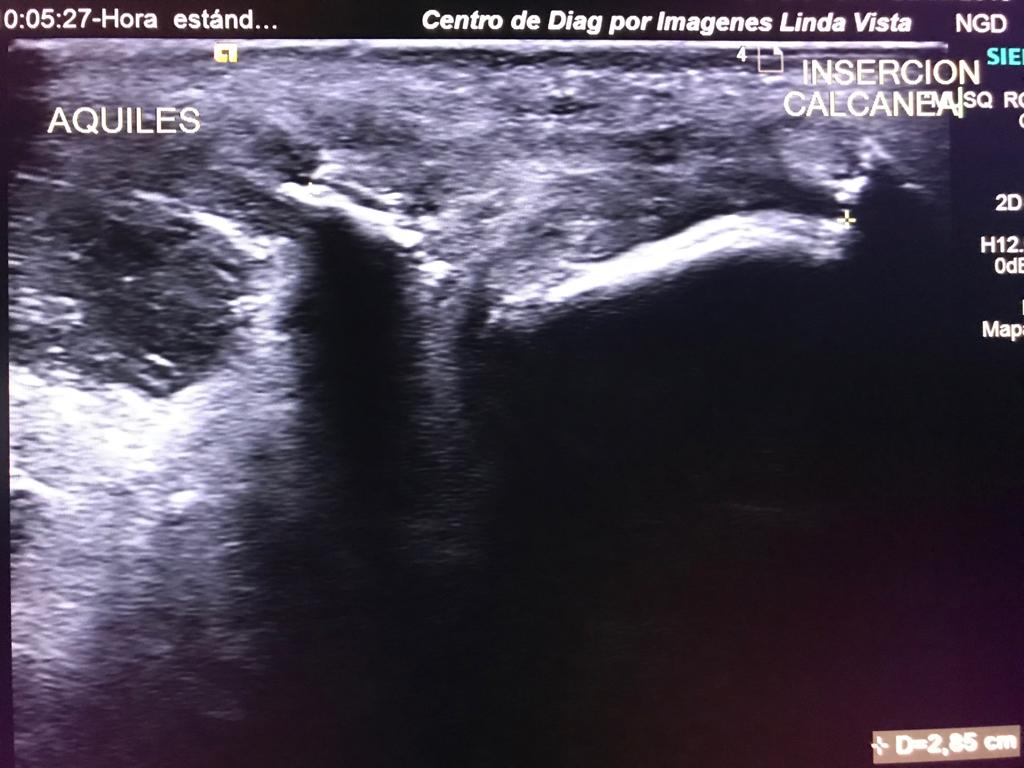

Ultrasonido de Tobillo. Femenina 55 años

Dra. Sterling Arróliga Selva Medico Radióloga-Resonancia Magnética. Cod. 12966